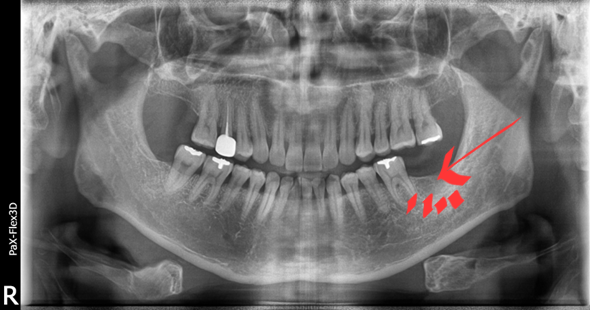

저희 병원 근처 회사에 다니시는 40대 남성분으로 사진에서 보시는 것과 같이 발치는 이미 되어있는 상태셨습니다.

(전) 2021-10-07

지속해서 시술을 미뤄오시다가 저희 네이버 리뷰를 보시고는 신뢰가 생겨 내원하게 되셨다고 말씀해 주셨는데요.

이전 병원에서 발치 당시, 뼈이식을 해야 할 수도 있다는 이야기를 들으셨던 터라 걱정이 많으셨지만,

저희가 진료했을 때는 뼈이식 없이 식립을 진행해도 괜찮다고 판단하여 그리 진행하였습니다.